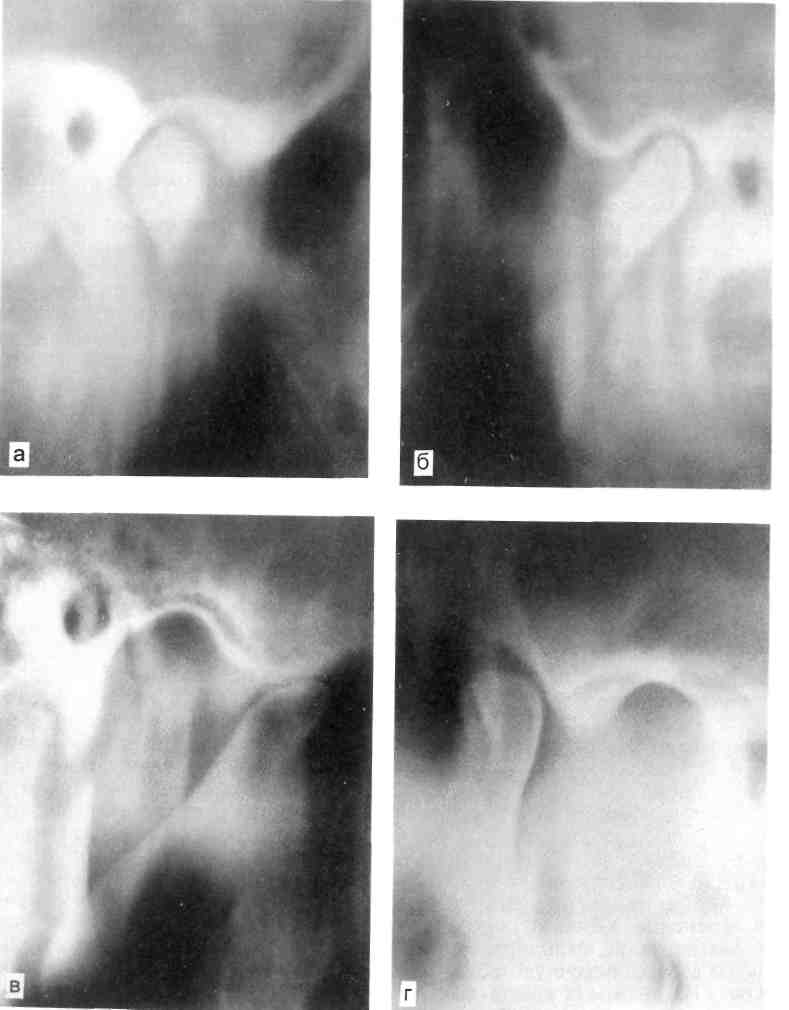

На томограммах при привычном положении нижней челюсти выяв­ляется уменьшение заднего отдела суставной щели по сравнению с пе­редним и верхним отделами, что свидетельствует о начале патологи­ческого процесса. На томограммах при максимальном опускании ниж­ней челюсти определяется увеличе­ние экскурсии суставной головки различной степени выраженности с расположением ее кпереди от вер­шины суставного бугорка (рис. 11.10).

Рис. 11.10. Полный передний вывих ВНЧС при его дисфункции. Томограмма.

а, б — с закрытым ртом; в, г — с открытым ртом (суставная головка вне суставной впади­ны).